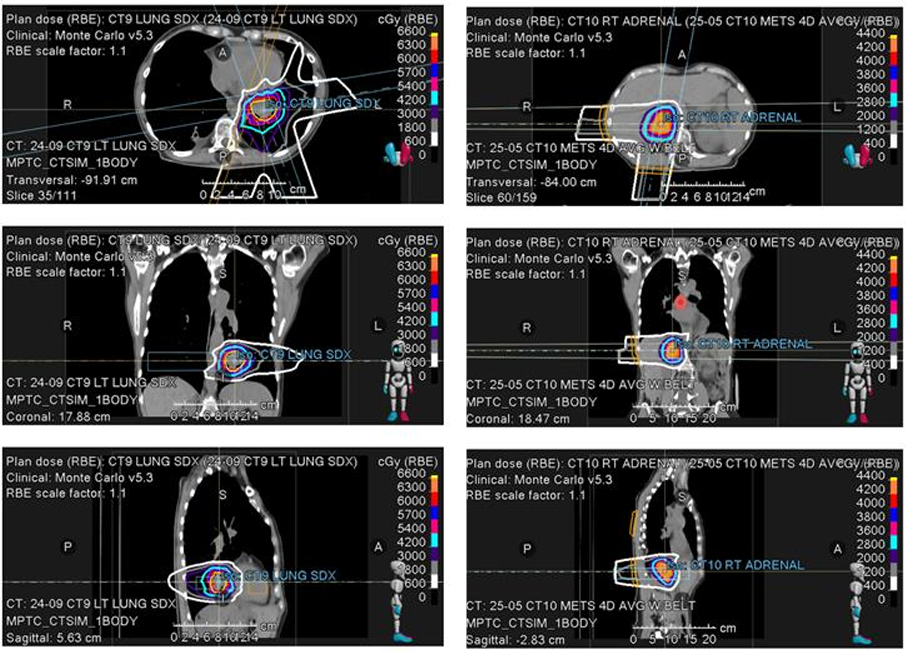

在Adagrasib治疗期间,患者经历数次局部进展,放射肿瘤科采用先进的质子治疗以保护重要器官:

2024年10月:左肺下叶结节进展。考虑到病灶靠近心脏且体积较大,实施强度调制质子治疗,60Gy/12次)。治疗期间短暂停用Adagrasib。

2025年5月:隆突下淋巴结及右肾上腺出现寡进展。

隆突下区域:利用质子笔束扫描技术(15次照射,每次3Gy),以避开关键纵隔结构。

肾上腺病灶:实施5次大剂量照射(每次8Gy)。

eb937012-54cc-4f01-a0a1-b50a67319e03.png